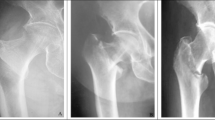

Once the sheep began bearing significant loads over the fracture leg at Week 2, n = 32 measurable radiographs were taken across the 8 subsequent weeks until sacrifice (2–5 each week). The weight that the sheep applied to the scale was noted with the radiograph number, and the indicator rod position was measured and compared to the applied load. At week 2, significant sensor rod movement was observed at 29 kg, and this continued until week 8. At week 8, a noticeable decrease in sensor movement was observed at all loads, and after further observation at weeks 9 and 10, the sheep was sacrificed. Figure 3 shows example radiographs for loaded and unloaded conditions at Week 4 when most displacement was apparent and Week 8 when motion had essentially stopped. The quality of the radiograph was imperfect because the animal could move, the source and detector were hand-held, and no antiscatter grids could be used due to variable positioning of source and detector. However, the indicator rod position was apparent in the canulation and the addition of boxes in Image J allowed for the measurement of rod position.

With confirmation that a fracture callus had indeed fully formed, the extracted femur was taken back to GSRC for axial testing. The femur was potted in Fast-Cast cement and subjected to axial loaded as outlined previously. At 400 N of load, the sensor rod did not show detectable movement using ImageJ analysis (Fig. 5).